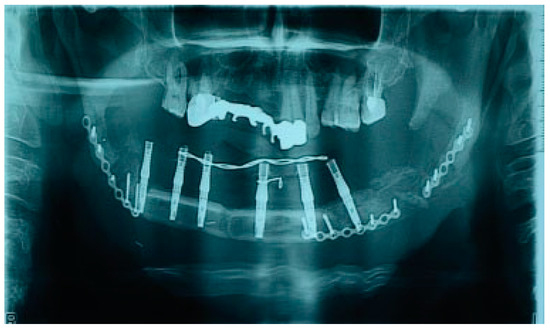

There were no significant complications postoperatively. Postoperative CT and OPG showed bone graft, dental implants, and reconstructive plate to be positioned in accurate anatomical relationship to each other and facial skeleton (Figure 8). A half year later, reconstructive plate was replaced by titanium miniplates (Figure 9).

Figure 8. Postoperative radiology: OPG.

Figure 9. Reconstructive plate was replaced by miniplates.